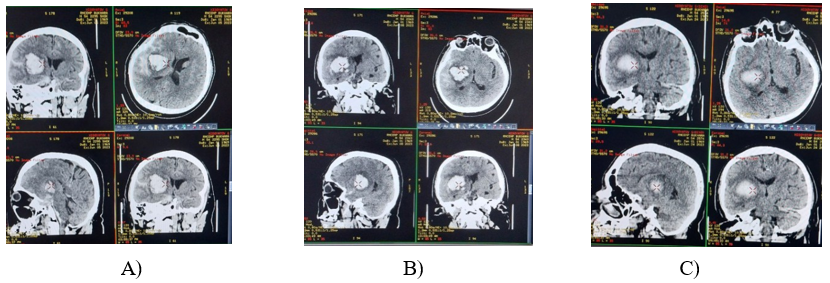

Dynamic neuroimaging control (MSCT of the brain) made it possible to obtain information about the state of the hemorrhage, the bruise zone, and the perifocal zone. Analysis of the obtained data from the MSCT study revealed that all patients in both groups had parenchymal and hemorrhages in the subarachnoid space and ventricles of the brain on the primary MSCT. In addition, congestion of the sulci of the cerebral cortex and narrowing of the basal cistern were signs of intracranial hypertension with symptoms of impaired consciousness. In patients of the main group, against the background of lymphotropic decongestant therapy on the second and third MSCT, regression of cerebral edema was evidenced by the appearance of signs of improvement in the ar chitectonics of the cerebral cortex, restoration of the normal sizes of the basal cisterns and ventricles of the brain (Figures 1 and 3). All these manifestations corresponded to positive neurological changes. And in patients in the control group, the above changes on MSCT of the brain appeared noticeably slowly (Figures 1 and 2).

A) B) C)

Figurer 1: MSCT of the patient. with hemorrhagic stroke of the main group (A – upon admission, B – on the 5th day, C – on the 10th day).